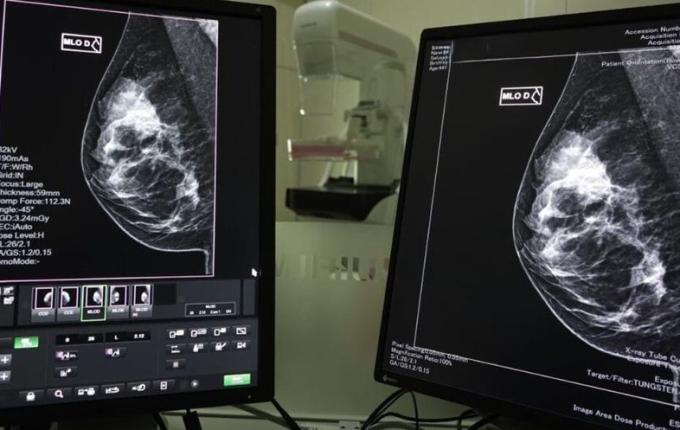

A detecção precoce do câncer de mama é fundamental para aumentar as chances de tratamentos menos invasivos e com maiores taxas de sucesso. As mamografias são realizadas pelo SUS, via Atenção Primária à Saúde, com prestadores dos municípios e Consórcios de Saúde.

Hospitais de gestão estadual, que prestam serviços de saúde da mulher e possuem mamógrafos, também realizam os exames.

O SUS garante acesso gratuito a medicamentos, exames, internações e procedimentos necessários. Ao identificar um nódulo ou qualquer outro sintoma suspeito, a recomendação é procurar uma Unidade Básica de Saúde (UBS) para atendimento. De lá, segundo a Secretaria de Saúde, o paciente é encaminhado para realização de exames, entre eles a mamografia, ultrassonografia e ressonância magnética.